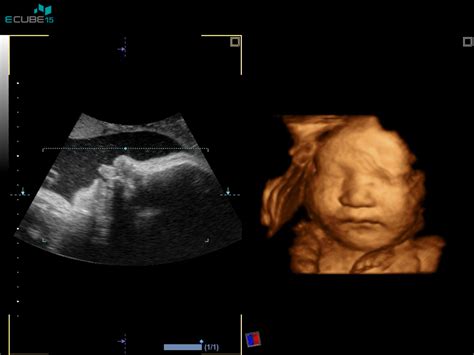

Nuhalna svetlina predstavlja prostor na vratu ploda, ki se nahaja med hrbtenico in kožo, napolnjen pa je s tekočino. Njegovo natančno merjenje poteka med ultrazvočnim pregledom v sklopu zgodnje morfologije, ki je eden najpomembnejših diagnostičnih postopkov v celotnem obdobju nosečnosti. Ta pregled omogoča zgodnje odkrivanje morebitnih kromosomskih nepravilnosti pri plodu, kar je ključnega pomena za nadaljnje spremljanje in načrtovanje.

Ultrazvočno merjenje nuhalne svetline je postopek, pri katerem se oceni debelina plasti tekočine na vratu ploda. Po velikosti nuhalne svetline lahko zdravstveni strokovnjaki sklepajo o morebitnih kromosomskih okvarah. Pomembno je poudariti, da povečana nuhalna svetlina ne pomeni nujno prisotnosti kromosomske nepravilnosti, vendar pa je pri približno 70 % plodov s kromosomskimi okvarami ta parameter povečan. Zato predstavlja pomemben signal za nadaljnje poglobljene preiskave.